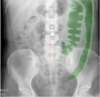

**Answer: Bowel wall inflammation** ## Footnote The descending colon is featureless with loss of the normal haustra. The right radiograph shows the inflamed bowel marked in green and the bowel wall thickening marked in light green. (You can also see an umbilical piercing.)